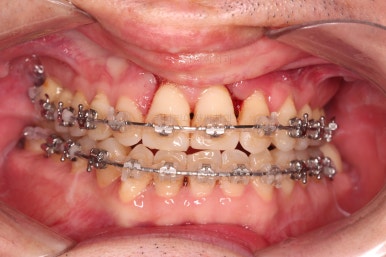

부산구순구개열교정 종료 시의 입안의 모습입니다.

위아랫니 정렬이 잘 되었고, 치아 갯수가 위아래가 다르지만 교합도 나쁘지 않게 마무리가 되었습니다.

대문니 2개가 예후가 안좋긴 하나 양옆 치아들과 유지철사로 부착해 두어 최대한 오래 조심히 써보기로 했습니다.

치열이 정렬이 잘 되었고요.

웃을 때 보이는 치열의 느낌, 얼굴과의 조화 등 모든 부분이 좋아졌습니다.